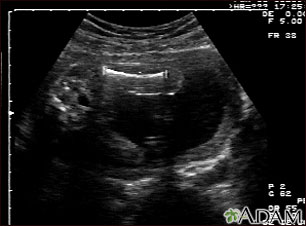

Ultrasonido de un feto normal; medidas del fémur

Ultrasonido normal a las 19 semanas de gestación en el cual se puede apreciar una imagen clara del fémur (hueso grande de la pierna) izquierdo, en el centro y hacia la parte superior de la pantalla.